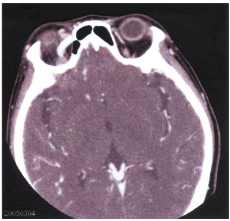

73 一位 24 歲男性,三週前曾發生車禍造成頭部外傷。主訴最近十天右眼紅腫,右眼球輕微突出,睡覺 時右耳隱約聽到咻咻聲,而來眼科求診。附圖為注射顯影劑後 CT 的眼眶影像,其最可能的診斷是: (A) carotid cavernous fistula (B) retrobulbar hematoma (C) traumatic edema of superior rectus muscle (D) myositis of superior rectus muscle